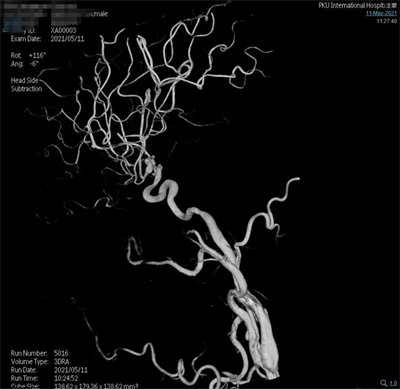

术前影像

脑动脉造影(外院,2021-5-10):双侧大脑中动脉分叉多发动脉瘤。

夹闭前造影